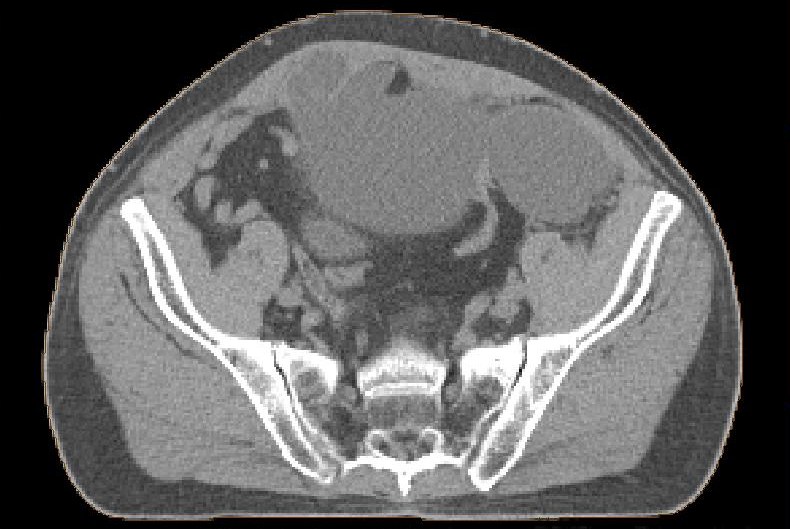

postoperative Lymphozele

Große Lymphozelen nach laparoskopischer pelviner Lymphonodektomie.